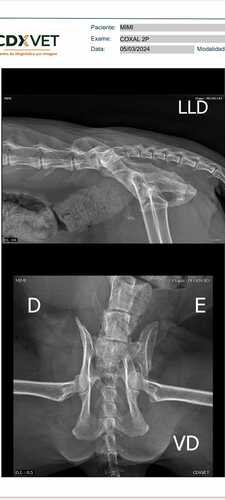

Oi pessoal, me chamo Lorraine, e nessa sexta feira (01/03) encontramos nossa gatinha Mimi sangrando na escada e com a parte traseira caída, ela ficou sozinha no quintal por volta de 1 hora, não sabíamos o que tinha acontecido, ela sempre foi extremamente dócil, nos a adotamos a 12 anos e ela nunca deu problemas. Levamos no veterinário, fizemos ultrassom, exame de sangue e realmente não fazíamos a menor ideia do que realmente aconteceu, no ultrassom constou lesão na bexiga, então realizamos um raio-X, e assim descobrimos que a Bacia dela quebrou. As únicas possibilidades que pensamos ate o momento é que algo prensou ela ou alguém a machucou (provavelmente a 2 opção pois a primeira é improvável). Ela está sem conseguir fazer suas necessidades por sentir muita dor, não somos ricos, e não temos mais condições de arcar com o veterinário, a cirurgia ortopédica mais a anestesia, com o enema (lavagem), e a internação inicial de apenas 48h ficou no valor de R$3.570,00, não temos como pagar esse valor, colocamos a vaquinha para R$4.200,00 para caso precise de mais algum dia de internação, pois cada dia sai no valor de R$220,00. Ela está sofrendo muito, não pode andar, nem ficar em pé por conta desse osso quebrado, ela já é idosa, muito carinhosa e dócil. Nós ajude a salvar ela por favor.